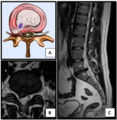

The majority of spinal disc herniations occur in the lumbar spine (95% at L4–L5 or L5–S1).[19] The second most common site is the cervical region (C5–C6, C6–C7). The thoracic region accounts for only 1–2% of cases. Herniations usually occur postero-laterally, at the points where the annulus fibrosus is relatively thin and is not reinforced by the posterior or anterior longitudinal ligament.[19] In the cervical spine, a symptomatic postero-lateral herniation between two vertebrae will impinge on the nerve which exits the spinal canal between those two vertebrae on that side.[19] So, for example, a right postero-lateral herniation of the disc between vertebrae C5 and C6 will impinge on the right C6 spinal nerve. The rest of the spinal cord, however, is oriented differently, so a symptomatic postero-lateral herniation between two vertebrae will impinge on the nerve exiting at the next intervertebral level down.[19]

Herniated disc at C6–C7 level

Cervical disc herniations occur in the neck, most often between the fifth and sixth (C5–6) and the sixth and seventh (C6–7) cervical vertebral bodies. There is an increased susceptibility amongst older (60+) patients to herniations higher in the neck, especially at C3–4.[21] Symptoms of cervical herniations may be felt in the back of the skull, the neck, shoulder girdle, scapula, arm, and hand.[22] The nerves of the cervical plexus and brachial plexus can be affected.[23]